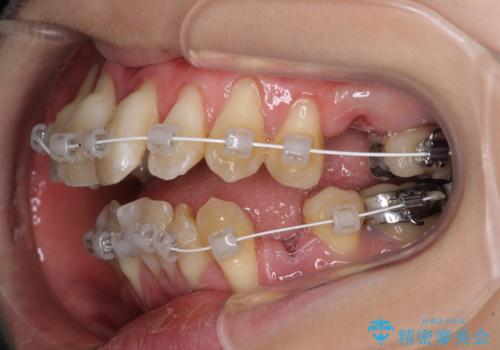

急速拡大装置 狭い骨幅を拡大した上で、顕著なデコボコを改善する抜歯矯正治療

- 審美装置

- 前歯のデコボコと唇の閉じにくさを気にして来院された患者様です。

上顎骨よりも下顎骨の幅が広く、更には下顎骨が左側に変位していたため、より良い咬み合わせを達成することを目的として、急速拡大装置を用いて上顎骨を拡大することとしました。

デコボコが強い上に、口元の突出感も気にしていたため、上下左右の小臼歯4本を抜歯して、ワイヤー装置にて矯正治療を行うこととしました。